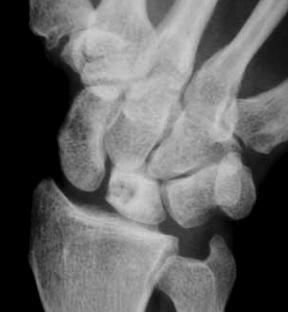

Diagnosis? Etiology?

Keinbochs